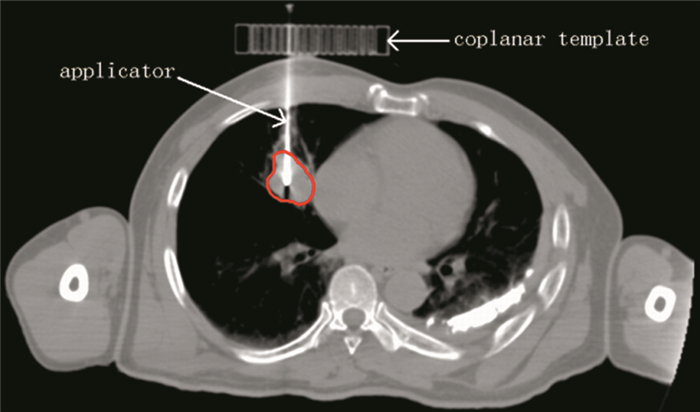

方法 回顾性分析28例接受模板辅助192Ir源大分割SABT治疗周围型肺癌患者的靶区与危及器官剂量,制作虚拟立体定向放射治疗(SBRT)计划与SABT计划进行剂量参数对比。

Methods We retrospectively analyzed the dose parameters of GTV and OARs of 28 peripheral lung cancer patients treated with template-assisted 192Ir-source hypofractionated SABT, and compared the dose parameters between SABT with virtual SBRT.